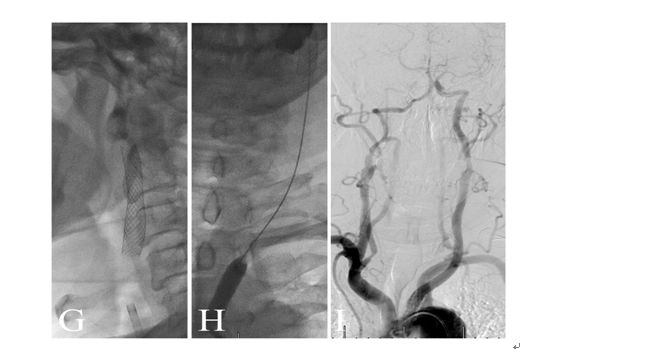

术前造影显示颈动脉C1-C4闭塞

颈动脉内膜剥脱后可见闭塞处血流缓慢。

近端闭塞处置入支架后,可见海绵窦段极重度狭窄

术中用小球囊2.5-20mm的球囊扩张海绵窦段狭窄处。

球囊扩张后,海绵窦段血流通畅。

术后一月复查CTA,见颈动脉闭塞段通畅。